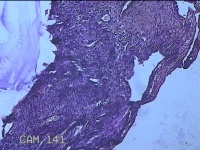

性别

女

年龄

43岁

临床诊断

异常子宫出血

一般病史

月经不规则2年余,发现宫颈赘生物近1年,活检外口可见多个赘生物。

标本名称

宫颈内容物

大体所见

灰白粉红色不规则碎组织1.2x0.8x0.3cm一堆。

图1